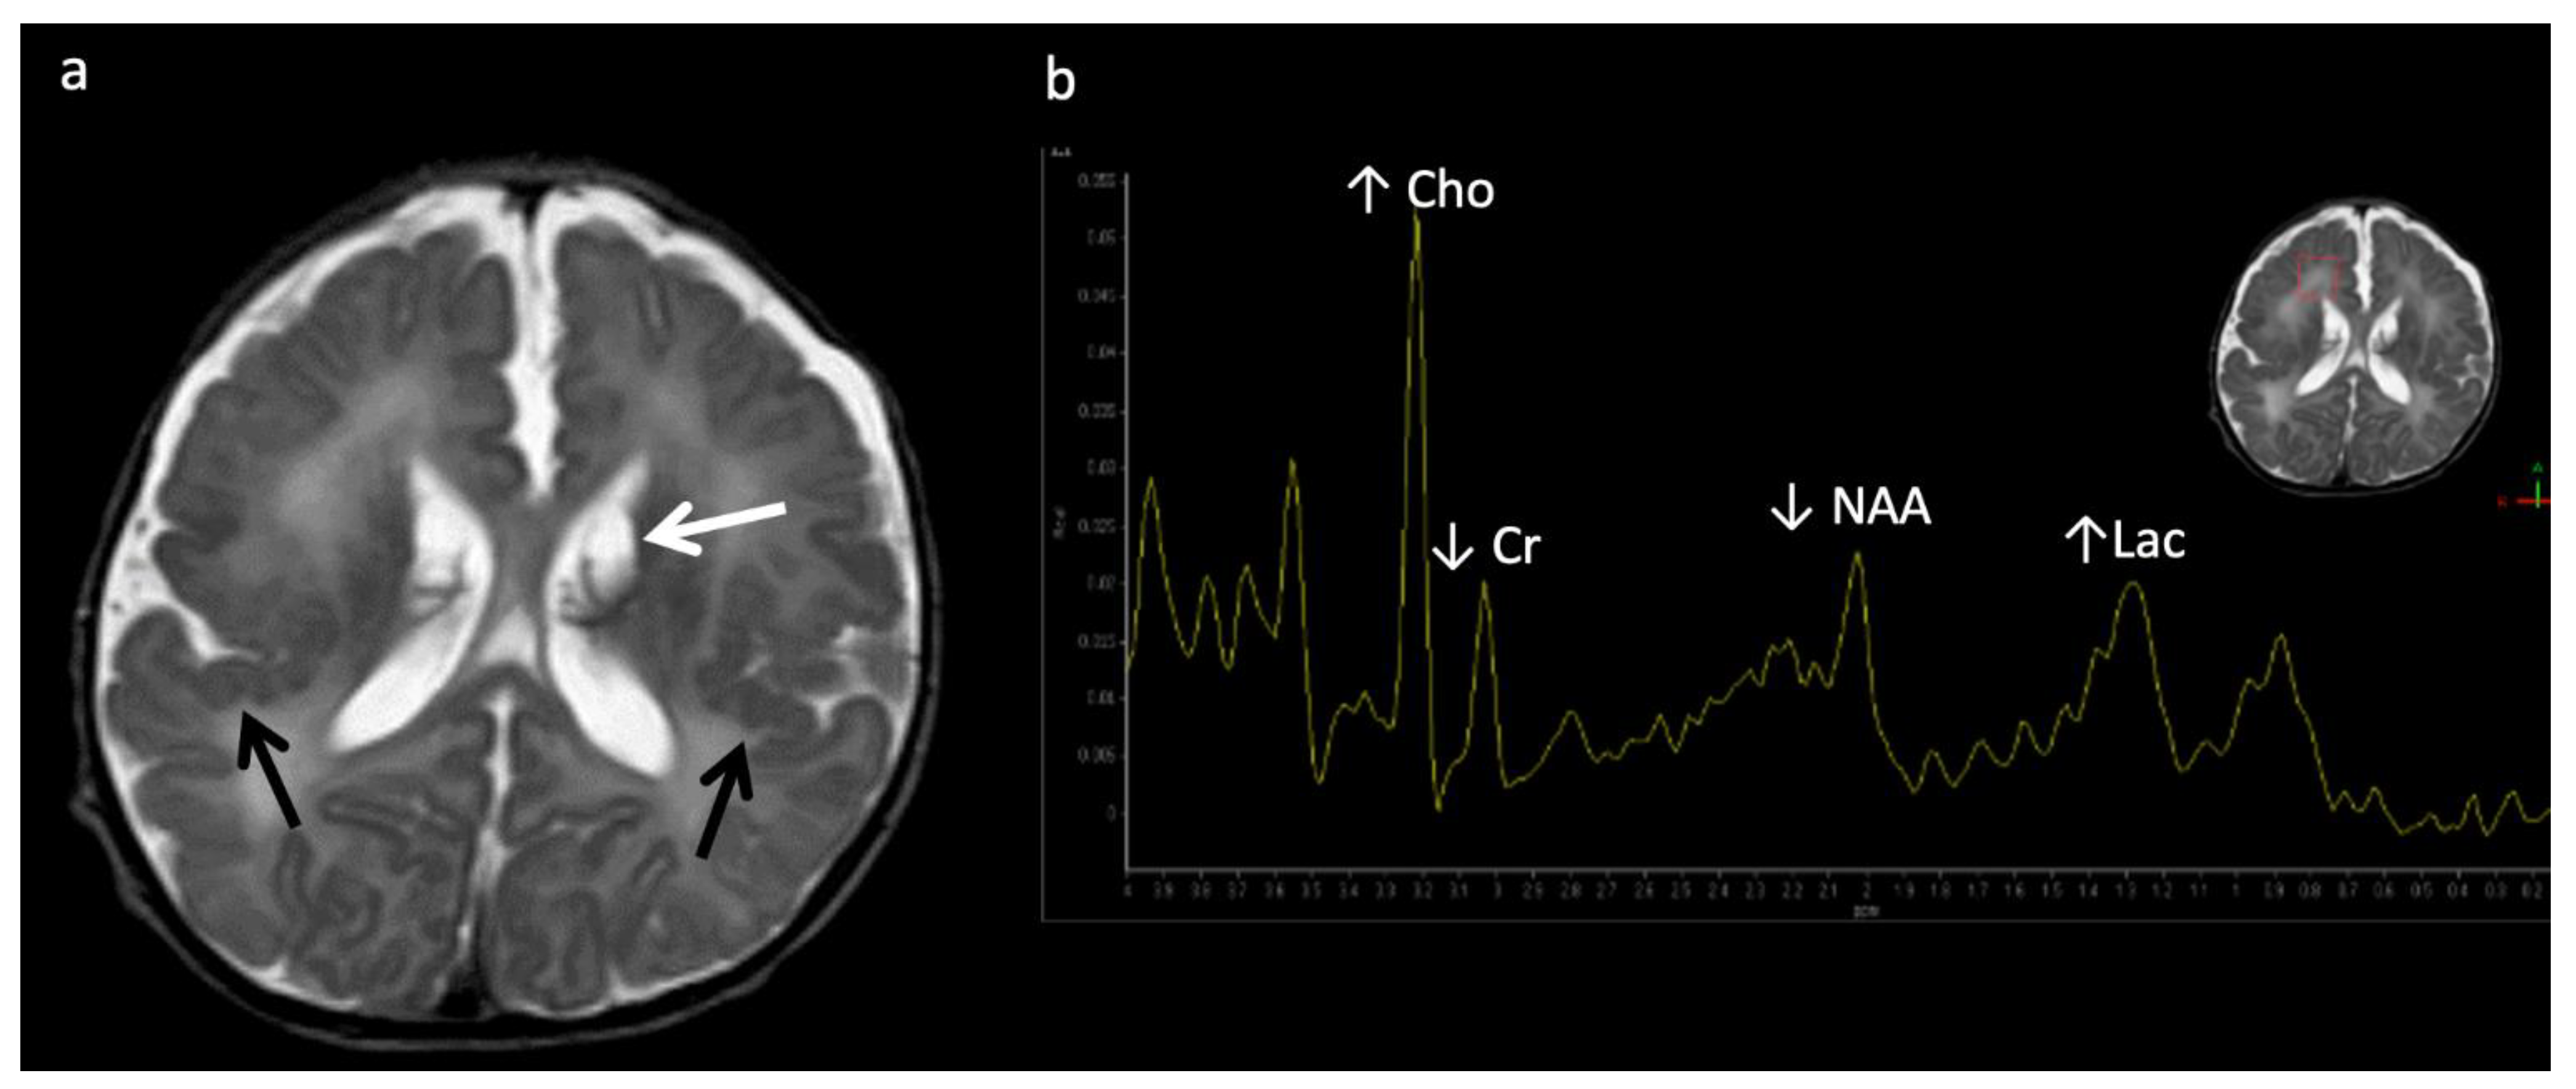

X-linked Adrenoleukodystrophy (ALD) (Figure 12): This peroxisomal disorder is due to a defect in oxidation of long-chain fatty acids resulting in their accumulation. Lesions usually initiate in the callosal splenium and spread into the forceps major, projectional fibers, and auditory and visual pathway; however, in a minority of cases, they may begin in the callosal genu and extend into the forceps minor and beyond [3,41]. Laminated zones of signal alteration in the involved cerebral areas are characteristic, with reduced diffusion and post-contrast enhancement during active demyelination and inflammation, The addition of X-ALD to newborn screen testing has brought about pre-symptomatic MR screening; these scans require careful scrutiny for early/mild changes with special attention to the corpus callosum [42]. Boys with X-ALD should be monitored with serial MRIs based on consensus guidelines [43]. MRS demonstrates decreased NAA and elevated Cho and mI, findings that can improve after successful stem cell transplant [44,45].

Figure 12.

Six-year-old male with X-linked Adrenoleukodystrophy (ALD). (a) Axial T2 and (b) DWI images reveal confluent T2 hyperintensity (a) and reduced diffusion (b) involving the callosal splenium and forceps major/peri-trigonal white matter (white arrows) with sparing of subcortical U-fibers. The pattern of involvement has a postero-anterior and centrifugal pattern. A zonal pattern of signal alteration with mixed diffusion abnormalities indicates acute on chronic demyelination related injury. (c) SV-MRS of the left periatrial white matter reveals decreased NAA (neuronal loss, decreased neuronal-axonal integrity, and/or decreased production), elevated Cho (increased membrane turnover), increased mI (neuroinflammation marker), and increased Lac (anaerobic metabolism).